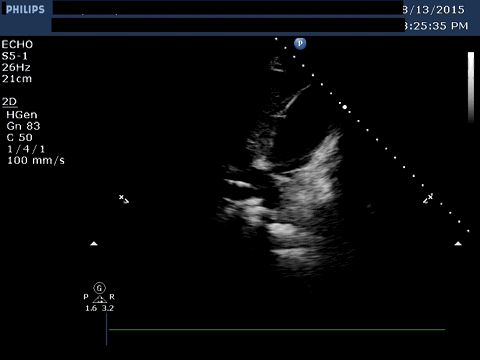

Image 1 shows a subcostal window of the inferior vena cava entering

into the right atrium. The guidewire is seen within the vena cava.

Interposed between the liver and the right ventricle is a large

pericardial effusion.